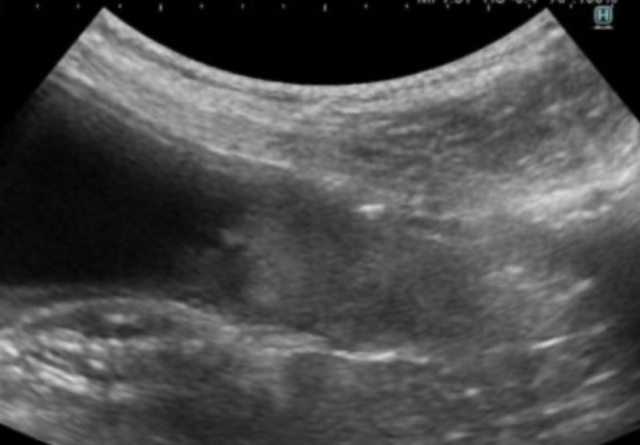

当院では約5秒で動物の全体をスキャンするCTがございます。これにより、動物への麻酔の負担を軽減して、撮影が行えます。また、動物の状態が悪い場合には麻酔をかけずに撮影を行うこともあります。撮影したデータは画像診断医“によって”正確な診断を行っております。動物のがんを早期に発見してあげることが何よりも動物に健康でいてもらえることに繋がりますので定期的な健診にも当院へお越しください。